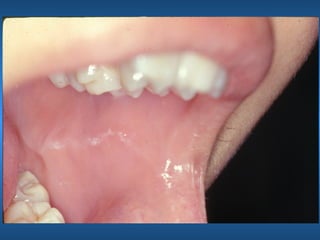

Língua Crenada ou

Indentação Língual

Linha de Oclusão